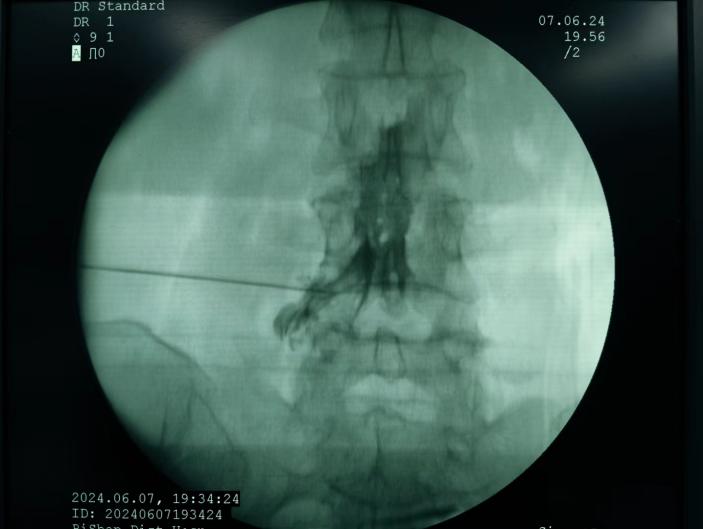

神經(jīng)阻滯,將藥物在影像引導(dǎo)下注射到受損神經(jīng)周圍,減輕炎癥和疼痛;

臭氧注射,通過向椎間盤內(nèi)注射臭氧,氧化髓核內(nèi)的蛋白多糖,降低椎間盤內(nèi)壓力,緩解癥狀;

射頻消融治療,連續(xù)射頻或脈沖射頻對椎間盤或神經(jīng)進(jìn)行干預(yù)治療,目的是減小神經(jīng)根周圍的壓力及對神經(jīng)的調(diào)控治療,從而達(dá)到緩解癥狀的效果;

膠原酶椎間盤化學(xué)溶解術(shù),是在影像引導(dǎo)下(C型臂X線機(jī)或CT),將膠原酶準(zhǔn)確地注射到突出的椎間盤內(nèi)及其周圍,使突出的椎間盤溶解并吸收,解除其對神經(jīng)根的壓迫,進(jìn)而緩解癥狀。

椎間盤射頻消融術(shù)、膠原酶椎間盤化學(xué)消融術(shù)